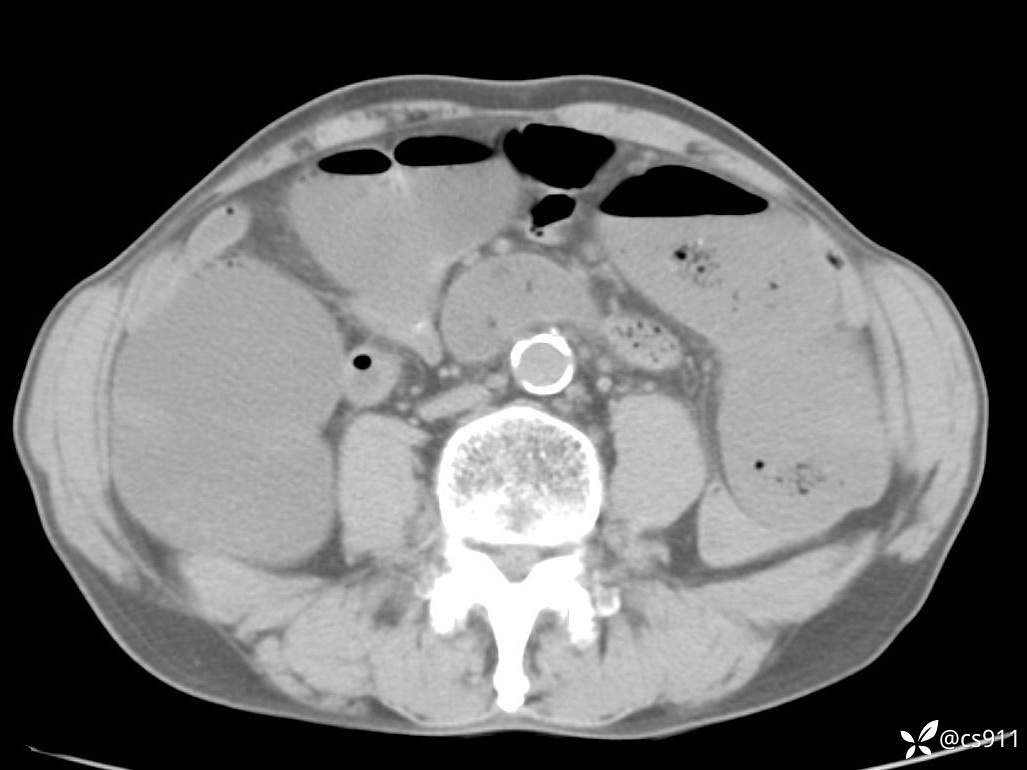

急腹症之急诊CT,原因?答案公布

男,77岁,腹痛、腹胀伴恶心呕吐1天。呕吐胃内容物,非喷射性呕吐,有咖啡色样胃内容物,诉有胃穿孔病史。查体:全腹平,下腹部压痛,全腹无反跳痛,叩诊呈浊音,移动性浊音阴性,肠鸣音减弱,1-2次/分。肛检:直肠未扪及明显肿物,可触及大量粪块。

血淀粉酶(AMY) HH 1859 U/L 35-135